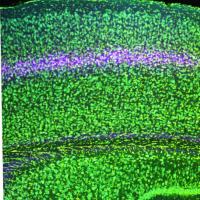

A section of cortex with colorfully labeled layers. Layer 4 stands out in a pinkish hue

Study probing visual memory, amblyopia unveils many-layered mystery

Researchers at the Picower Institute at MIT have discovered cellular mechanisms behind amblyopia and visual memory.